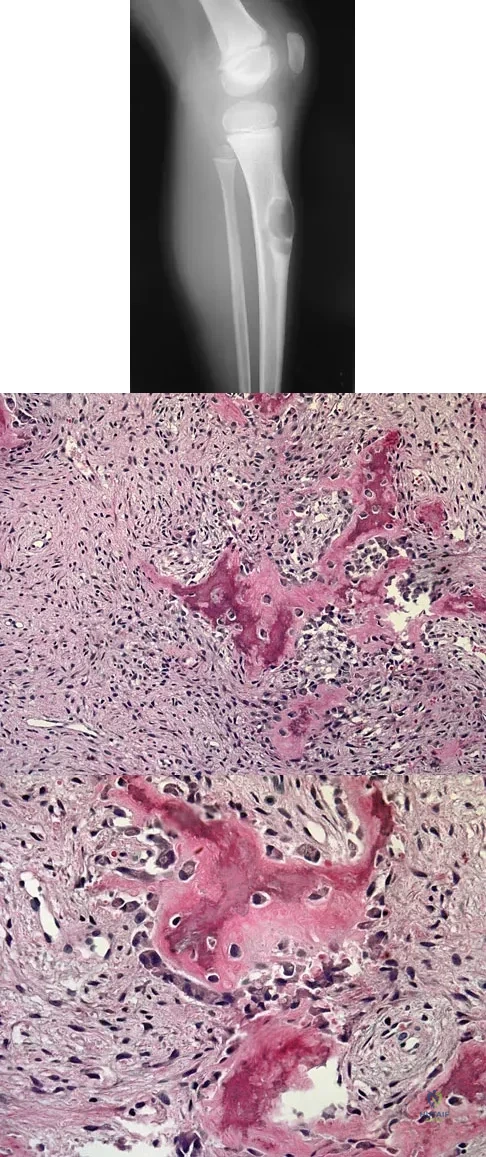

What is the second most common primary bone malignancy in children?

A 6-year-old boy presents with a mass and a lucent lesion involving the tibial shaft as seen in Figure 17a. The mass is mildly tender to palpation. The bone scan is focally hot in the tibia. Biopsy specimens are shown in Figures 17b and 17c. What is the most likely diagnosis?